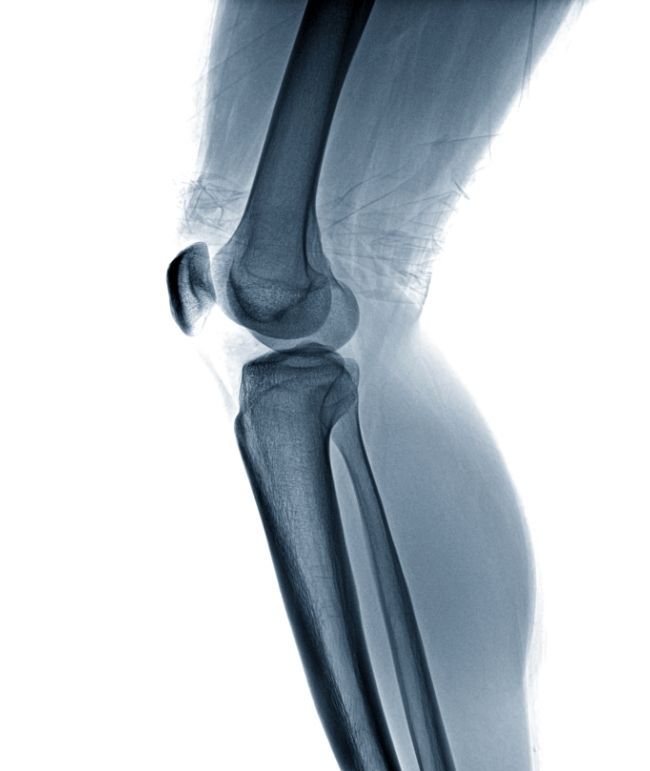

Nicht nur Leistungs-, sondern auch Hobbysportler kennen das: Das Kreuzband reißt, das Sprunggelenk ist verstaucht oder eine Verletzung der Patellasehne tritt plötzlich auf. Nun ist ein erfahrener Arzt für Sportverletzungen gefragt, der dafür sorgt, dass die Verletzung schnell wieder heilt. Immerhin sollen Ausfallzeiten vom Training so kurz wie möglich gehalten werden. Dr. Frisee ist Ihr Sporttraumatologe mit Erfahrung.

OA Dr. med. univ. Florian Frisee hat sich bereits frühzeitig in seiner Laufbahn auf die minimalinvasive Chirurgie spezialisiert, dank der keine großen Operationen nötig sind. Einer seiner Behandlungsschwerpunkte ist die arthroskopische Kniechirurgie, bei der die Behandlung eines Knieschadens mit minimalem Eingriff möglich ist. Hilfreich sind hier die über 20 Jahre Erfahrung im Bereich der Arthroskopie.